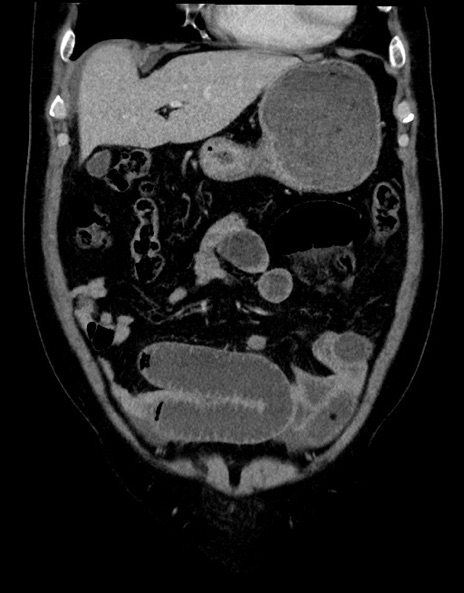

横断像

【症例】70歳代男性

【主訴】腹痛

【現病歴】今朝から腹痛あり。全体的に痛い。特に左上の方。排ガスが今日はない。冷や汗が出る。

【既往歴】直腸癌術後

【身体所見】左側腹部〜上腹部に圧痛あり。腹膜刺激症状明らかなではない。軽度反跳痛。左下腹部に術後瘢痕あり。

【データ】WBC 7700、CRP 0.02